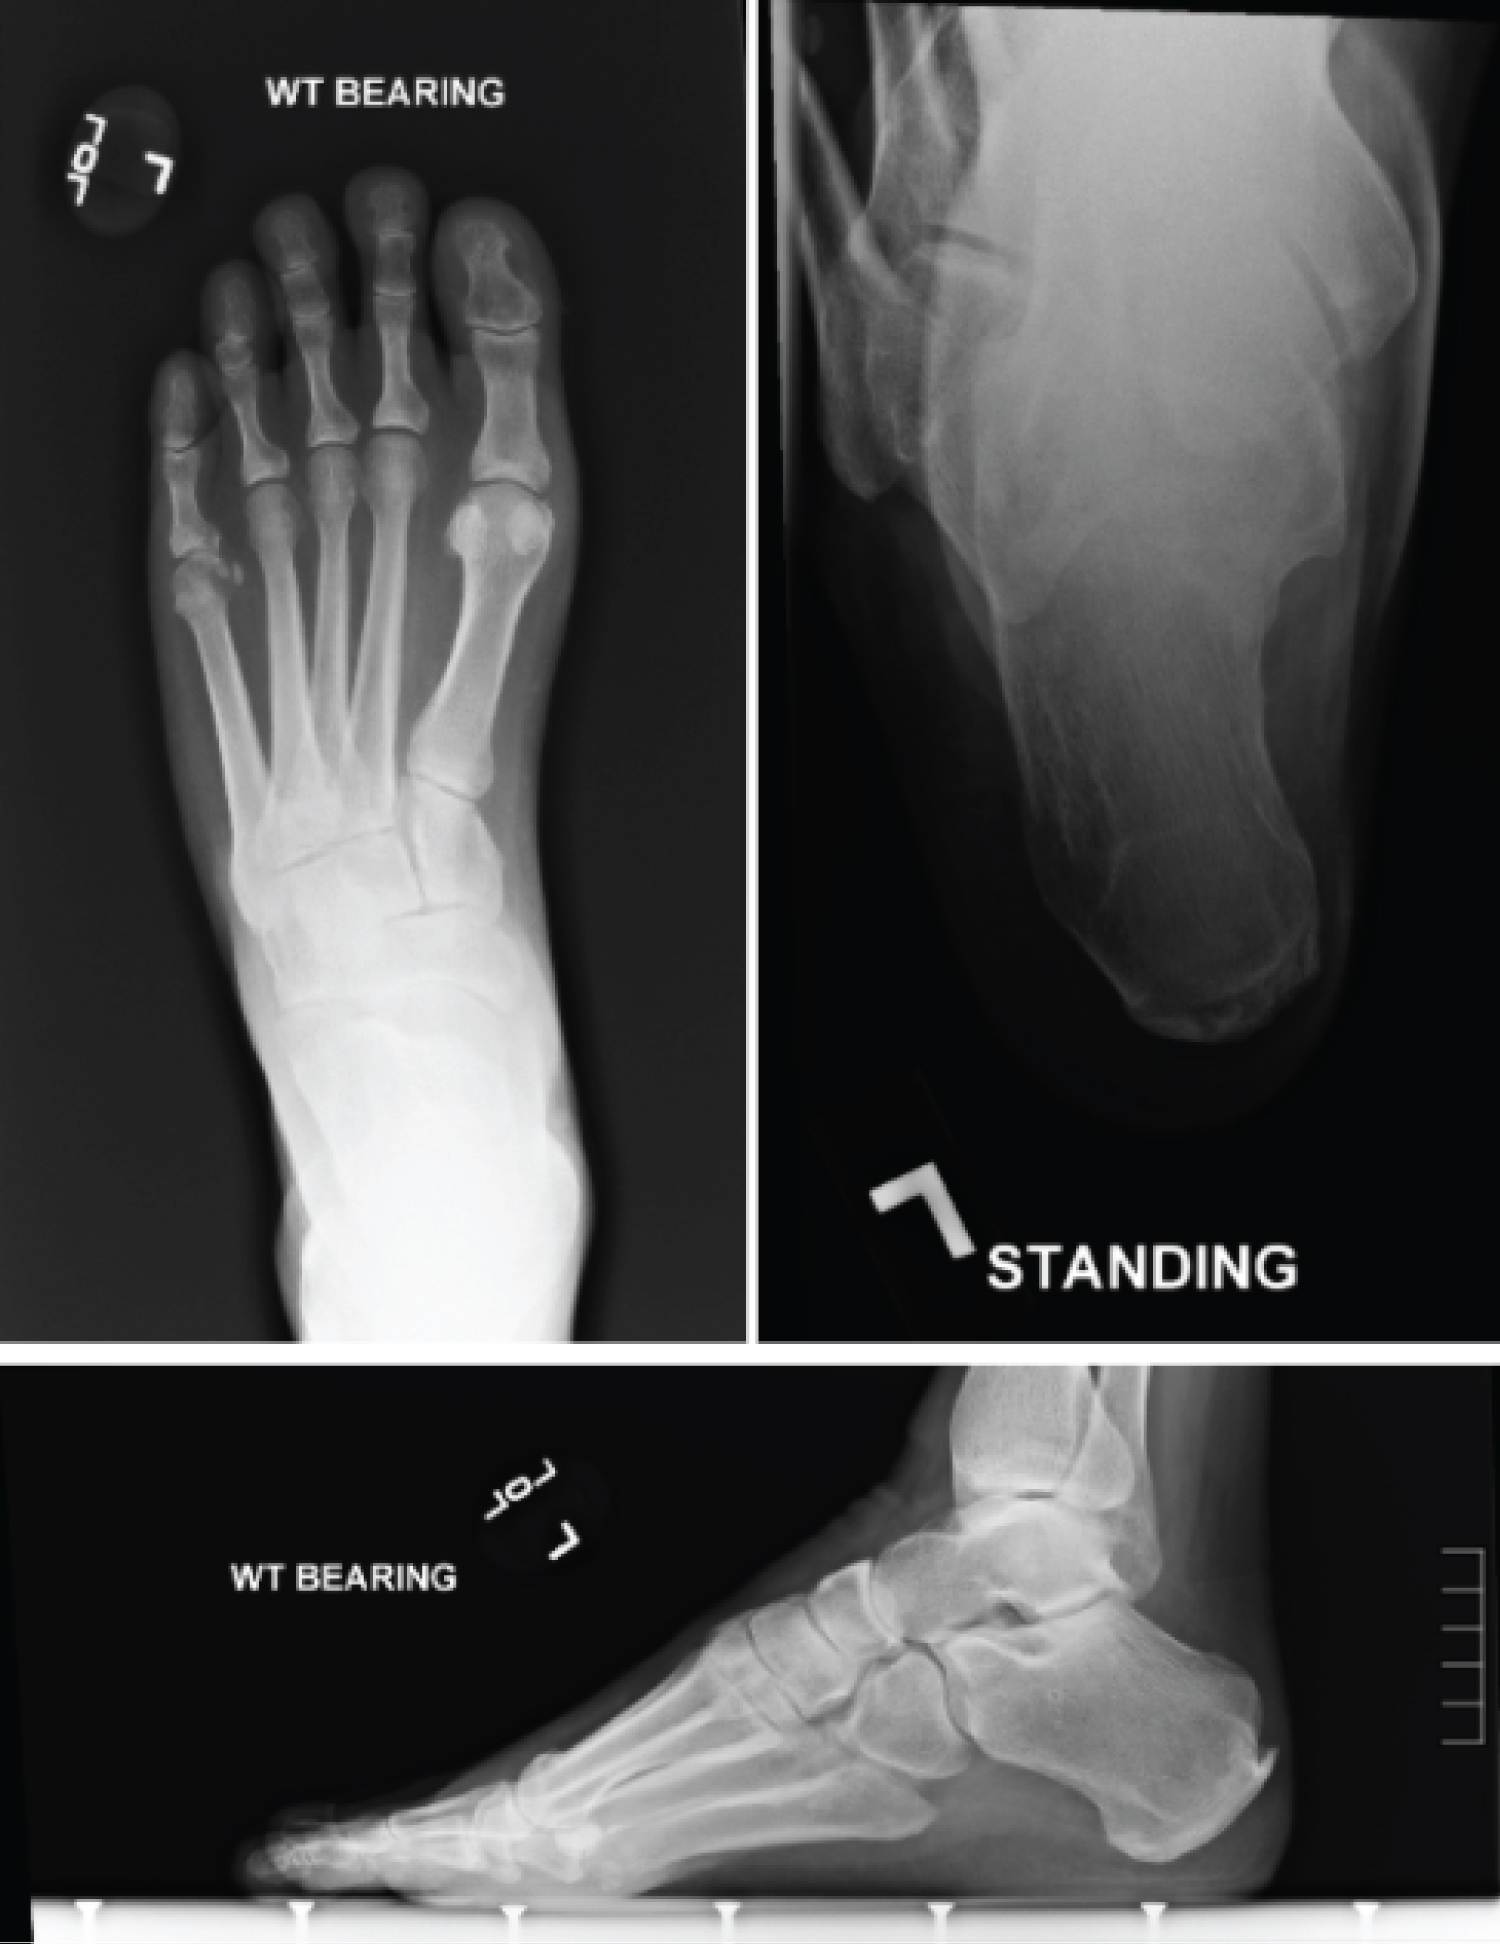

On physical examination there was a lack of epicritic sensation to the feet bilaterally, generalized tenderness to both feet, this was most notable in the plantar arches along the prominent plantar medial band of the plantar fascia. Notable cavus foot type bilaterally with the left slightly worse than the right. Resting calcaneal stance revealed a varus attitude of the calcaneus on both feet, which was non-reducible with the Coleman block test. Manual muscle testing revealed weakness in DF, PF, inversion, eversion with 4/5 strength throughout, with notable mild peroneal muscle fatigue. Gait analysis demonstrated abnormal and rapid subtalar joint supination during initial heel strike and supinated position of the STJ throughout the stance phase of gait. There was no ankle instability, peroneal tendon pain, and no pain laterally on the calcaneus over the peroneal tubercle (Figures 2, Figure 3 and Figure 4: Clinical Images).

Standard views of the feet were obtained along with calcaneal axial view, most notable for varus attitude of the calcaneus, increased inclination of the calcaneus, increased lateral Meary's angle, and increased talar coverage (Figure 5). This all correlated clinically with the cavovarus deformity noted.

Figure 5: Radiographs of a patient with CMT. Top left: weight bearing AP view, top right: weight bearing calcaneal axial view, bottom: Weight bearing lateral view. View Figure 5